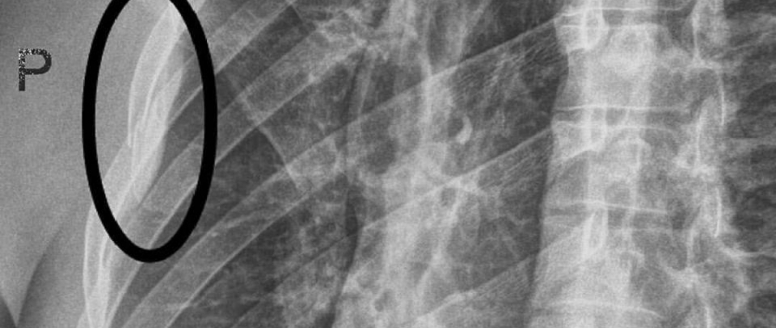

Po návratu z úspěšného závodu SP z Garmisch – Partenkirchenu si nechal Kryštof Krýzl v už doma v Praze vyšetřit bolavý hrudník. Roentgen bohužel odhalil frakturu jednoho žebra. To není před blížícím se mistrovstvím světa příjemná zpráva, ale Kryštof dokáže úspěšně závodit i se zlomeninou. Tu si totiž přivodil už 24. ledna v nočním slalomu ve Schladmingu, když v prvním kole chytil špicara a kolenem si přitom narazil do hrudníku. Zvládl s tím ještě dva dny lehce potrénovat a pak úspěšně zdolat obří slalom SP v Ga-Pa, kde dojel 24. a bral sedm bodů do hodnocení disciplíny v SP. „Říkal sem si, že není něco v pořádku, tak jsem šel hned po příjezdu domů na roentgen a ukázalo se, že je to zlomené. Tréninky před Garmischem jsem jel pod prášky proti bolesti, na závod jsem je ale na doporučení vysadil. Na MS to nebude jiné.“ Přejeme co nejrychlejší uzdravení a těším se na další výkony!

Photo: FB K.Krýzl